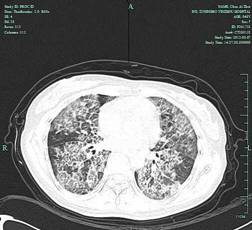

陈女士,48岁,5年前曾体检发现两肺弥漫性病变,2007年6月在我科经支气管镜肺活检及支气管灌洗等确诊肺泡蛋白沉积症。先后于2007年在我院及2010年两次行双侧全肺灌洗,病情得以改善。但4月前陈女士无明显诱因出现活动后气促,伴咳嗽,近期至我科门诊复诊,胸部CT提示肺内病变进展明显而入院。入院后我科在俞万钧主任医师的带领、组织下3月9日及3月16日再次对陈女士行全麻下左、右全肺灌洗术。该术过程相对复杂,需双腔气管插管行双肺隔离,一侧肺通气情况下,对另侧肺进行灌洗,总灌洗液体量27500毫升,术后患者常规入住ICU短时监护,不仅麻醉技术要求高,对我院呼吸科、麻醉科、放射科、重症监护病房等多科协作水平亦是考验。经治疗患者气促明显改善,病情稳定,今日好转出院。该手术再次顺利实施,并得以改进,体现了我院在该病诊治方面技术水平居宁波市前列。